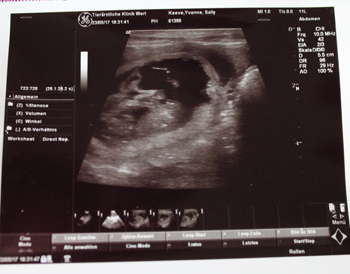

Beim gestrigen Ultraschalltermin, dem ich ja sehr ruhig ins Auge sehen konnte, weil ich ja schon genau wußte das Sally tragend ist, wußten wir gar nicht welches der vielen Q-ueridos wir uns zuerst ansehen sollten. Wo auch immer der Schallkopf hin wanderte, mindestens eine gefüllte Blase war schon dort. Meine Tierärztin legt sich mit der Anzahl der Welpen auch nicht fest, sagte aber 7 + X. Ich denke jetzt nicht an vorherige Würfe bei denen die im Ultraschall gesehene Welpenanzahl verdoppelt in meiner Wurfkiste lag. Das wäre dann doch zuviel des Guten. Röntgen werden wir Sally nicht, bei großen Würfen ist auch da dann nicht mehr 100%ig zu sagen wie viele erwartet werden denn sie überlagern sich dann.

Sally machte die Prozedur super entspannt mit, es wurde ein klitzekleiner Teil Bauch rasiert und dann ging es ans fotografieren. Bei den Zwergen ist ein kräftiger Herzschlag bereits jetzt auf dem Monitor erkennbar gewesen.